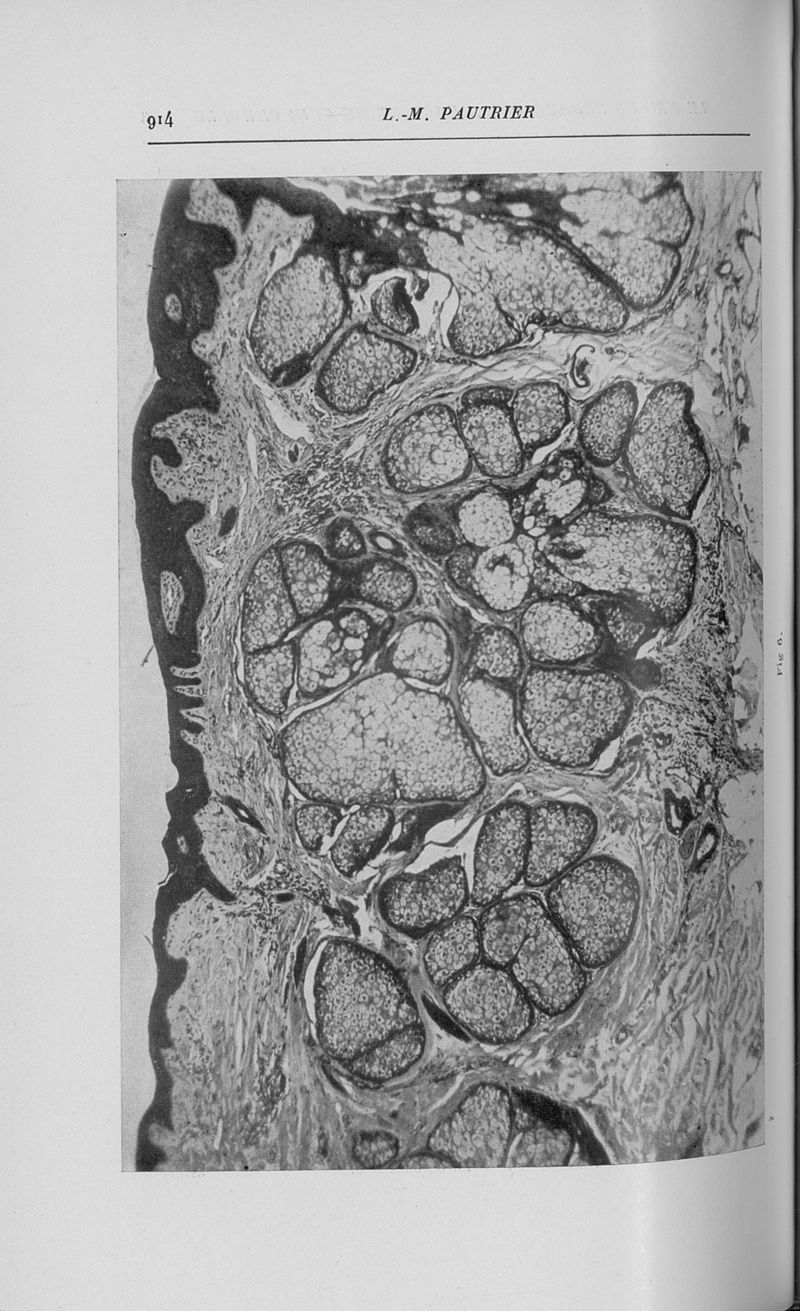

Annales de dermatologie et de syphiligraphie.

7ème série, tome VII. - Paris : Masson, 1936.